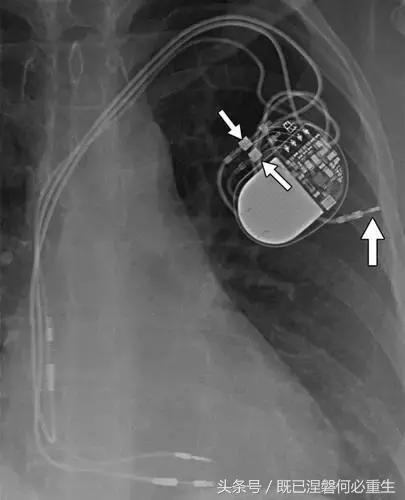

图5AB 在两个不同的患者电极错位和心室穿孔的例子。A,72岁的女性电极错误。 正位(A)和外侧(B)胸部X光片显示圣犹达医学双心室植入式心律转复除颤器与上腔静脉不适当的心房导线位置。 心房导联(箭头,A和B)的尖端高于右心房的水平,并且已经不适当地定位在上腔静脉中。 注意冠状窦引线(箭头B)的正常位置是在侧向投影中右心室(RV)引线的后方。

图5C,70岁女性心室穿孔。 正位胸片显示,圣犹达医疗双室起搏器的RV导联(箭头)超出心室轮廓。 心肌穿孔很少会导致放血或压塞。 患者没有受到并发症或随后的铅改变的不良影响(修订电极显示)。 心室穿孔可能导致对膜片的不适当刺激。